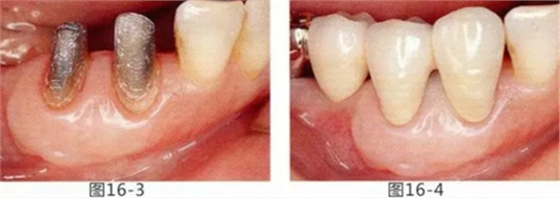

為了改善修復(fù)體周圍的環(huán)境,通過FGG(游離齦移植)來獲得附著齦的病例

有3~4mm牙周袋并且沒有附著齦的存在,系帶也在牙頸部附近位置的病例。通過FGG(游離齦移植)獲得附著齦同時(shí)切除系帶后,即使經(jīng)過了很長(zhǎng)時(shí)間,牙齦邊緣依然保持安定的狀態(tài)。

圖16-1 右3,4牙周袋探診值為3~4mm,基本沒有附著齦。右下3部位的系帶也附著在牙頸部附近,由于清潔困難而引發(fā)了炎癥。

圖16-2 由于磨牙部缺失,為了能夠進(jìn)行固定修復(fù)而在右下6位置植入種植體,制作右下3,4,5,6固定橋冠。為了增加基牙右下3,4周圍的附著齦,在實(shí)施FGG同時(shí)去除系帶。

圖16-3 獲得了足夠附著齦,可以抵抗刷牙等外部刺激。

圖16-4 獲得充分附著齦,易清潔的狀態(tài)。修復(fù)體之間的鼓形間隙大小均一也使清潔性得到提升。

圖16-5 佩戴最終修復(fù)體3年后的狀態(tài)。

圖16-6 佩戴最終修復(fù)體11年后的狀態(tài)。無牙齦萎縮保持著安定狀態(tài)。

圖16-7 配戴最終修復(fù)體18年后的狀態(tài)。